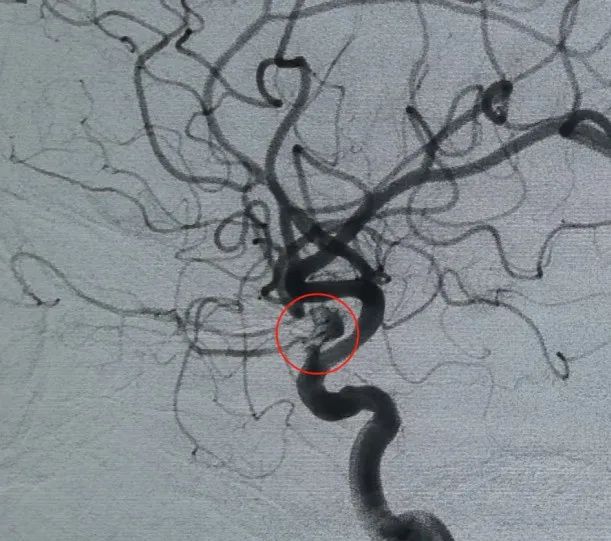

Diagnostic: Anévrisme de l'artère ophtalmique du segment C6 de l'artère carotide interne gauche

L'accès vasculaire a été établi par la ponction de l'artère fémorale, et un Perdenser®La bobine 3D de 6mm × 20 cm a été déployée pour former un panier, réalisant l'apposition stable de mur et fournissant l'appui intrasacculaire sûr. Cela a été suivi par l'insertion d'un Perdenser®Bobine 3D de 6mm × 15 cm pour perturber le flux sanguin dans le sac fille lobulé.

Un Perfiller®Bobine expansible de 3mm × 6 cm et un Perfiller®Une bobine expansible de 3mm x 2 cm a ensuite été placée pour compléter l'occlusion du cou. Par la suite, une Nuva®Le déviateur d'écoulement (TJED-D-5.0-16) a été livré et déployé à travers le col de l'anévrisme. L'angiographie de suivi dans les vues antéropostérieures et latérales a confirmé une excellente couverture, une bonne apposition de la paroi et une radiopacité claire, avec une stagnation marquée du contraste.